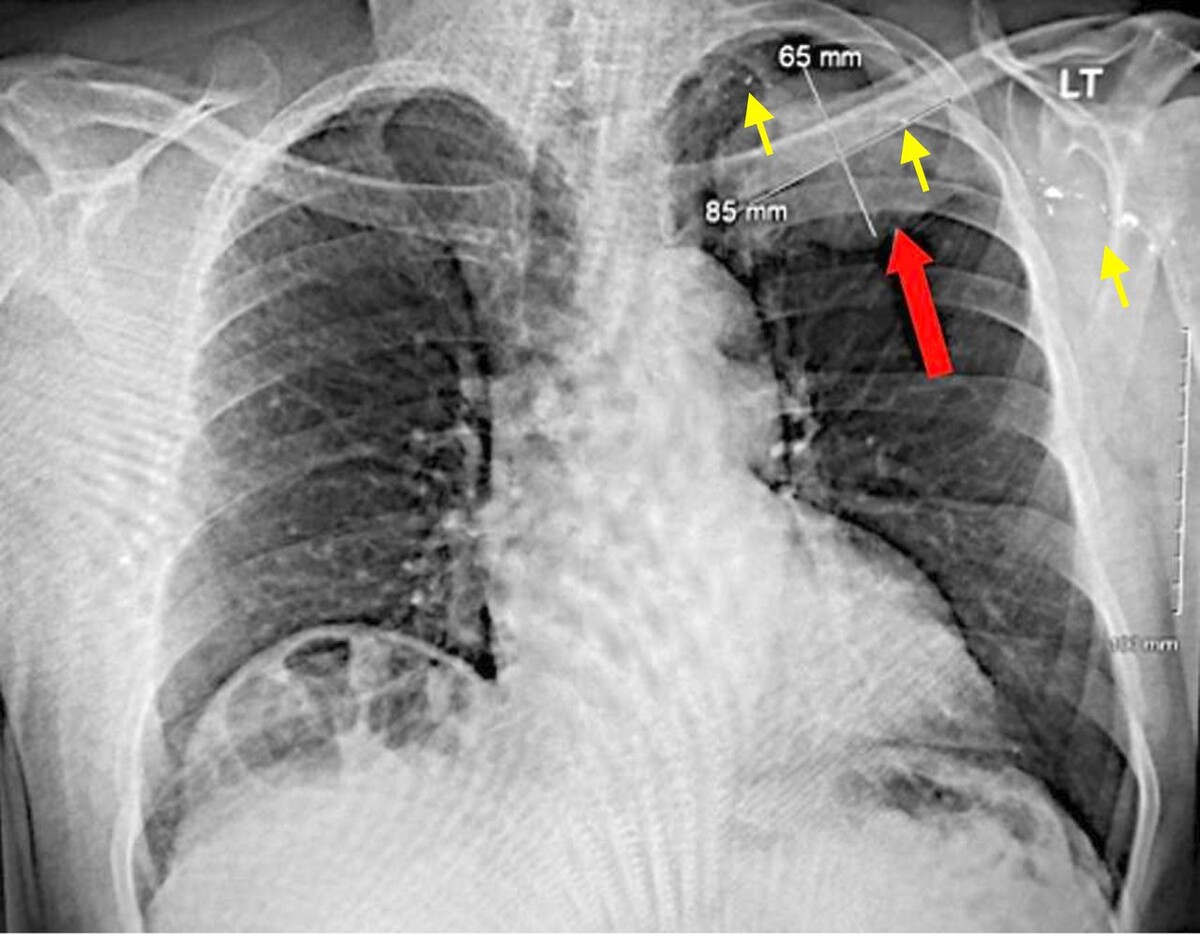

При дополнительном обследовании в его левом легком было обнаружено образование размером 7,6 × 7,5 сантиметра и баллистические осколки в этом образовании, левой подмышечной впадине и заднем средостении, которые сохранились у него после огнестрельного ранения, полученного 45 лет назад. В анамнезе у пациента не числилось онкологических заболеваний, однако он страдал гипотиреозом и дислипидемией. Также мужчина сообщил, что он употреблял табак в течение 37,5 года, но бросил курить три десятилетия назад.

Позитронно-эмиссионная томография выявила изолированное образование в левой верхней доле легкого с локальным поражением грудной стенки без признаков метастазирования. Биопсия легкого подтвердила диагноз мелкоклеточного рака легкого. Врачи удалили пораженную долю легкого вместе с регионарными лимфоузлами.